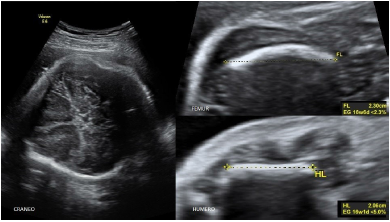

Se presenta el caso de una primigesta de 20 años de edad con 30 semanas de edad gestacional por ecografía precoz. Acudió al servicio de ecografía con diagnóstico de acondroplasia fetal, sin antecedentes personales ni familiares de importancia con relación a patologías de orden genético. Al examen ultrasonográfico se halló ponderado fetal de 2 323 g (p12 para la EG), fémur corto (p< 2DE) y curvo, tórax estrecho (circunferencia de 172 mm cortas, abdomen protuberante, macrocefalia DBP de 93 mm (>p 97,7%) CC de 319 mm (>p 97,7%), con cráneo en forma de trébol, frente prominente y aplanamiento nasal; relación fémur-pie de 0,4 (figuras 1 y 2). Otro hallazgo fue la presencia de polihidramnios leve (pozo mayor de 8,1 cm). No se encontraron malformaciones cardiacas. La reconstrucción 3D evidenció el acortamiento de los miembros superiores e inferiores y las características faciales (figura 3). De acuerdo a los hallazgos, se planteó el diagnóstico de TD, informando a la familia acerca del grave pronóstico del feto. El parto vaginal se dio una semana después, con un recién nacido vivo de sexo masculino de 2 015 g, Ápgar 2 al minuto y 5 a los 5 minutos, requiriendo intubación endotraqueal y soporte ventilatorio. Fue hospitalizado en UCI neonatal con el diagnóstico de insuficiencia respiratoria. El estudio radiográfico evidenció costillas acortadas, con los huesos largos de los miembros superiores e inferiores cortos y curvos (figura 4). El neonato falleció por insuficiencia respiratoria a los 7 días.

Un aspecto importante ante un caso de displasia esquelética es establecer el riesgo de letalidad. Si bien las malformaciones cardiacas o cerebrales de por sí pueden establecer pronóstico, para los casos que no las presentan la posibilidad de muerte está principalmente asociada a problemas de insuficiencia respiratoria por hipoplasia pulmonar(5,13,14). Se ha propuesto muchos marcadores; entre los de aplicación más fácil podemos mencionar la relación longitud de fémur/circunferencia abdominal (FL/AC) menor de 0,16(13,15), la circunferencia torácica (CT) menor al 2,5 percentil(13,16) y la relación CT/AC menor al 5º percentil(13). Entre estos marcadores, el de mayor poder predictivo es la relación FL/AC menor de 0,16; en el caso presentado se encontró una relación de 0,07 y el resultado perinatal fue muerte a los 7 días.